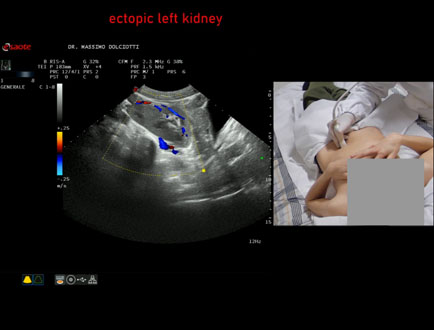

Data inserimento: 31/03/2026

Ecografia del: 16/03/2026

Strumento: Esaote MyLab Eight

Sonda: Convex Multifrequenza 1-8 MHz

Età Paziente: M 12 anni

Motivazione dell'esame: riscontro occasionale di ectopia renale sinistra

Commento all'esame: le immagini ed il video documentano il rene sinistro ectopico in sede pelvica, di ecostruttura regolare e morfovolumetria normale, con diametro bipolare di 99 mm (v.n. 90-120 mm) x 37 mm, non dilatazione della via escretrice sinistra.

Conclusioni: rene sinistro ectopico (ectopic left kidney).